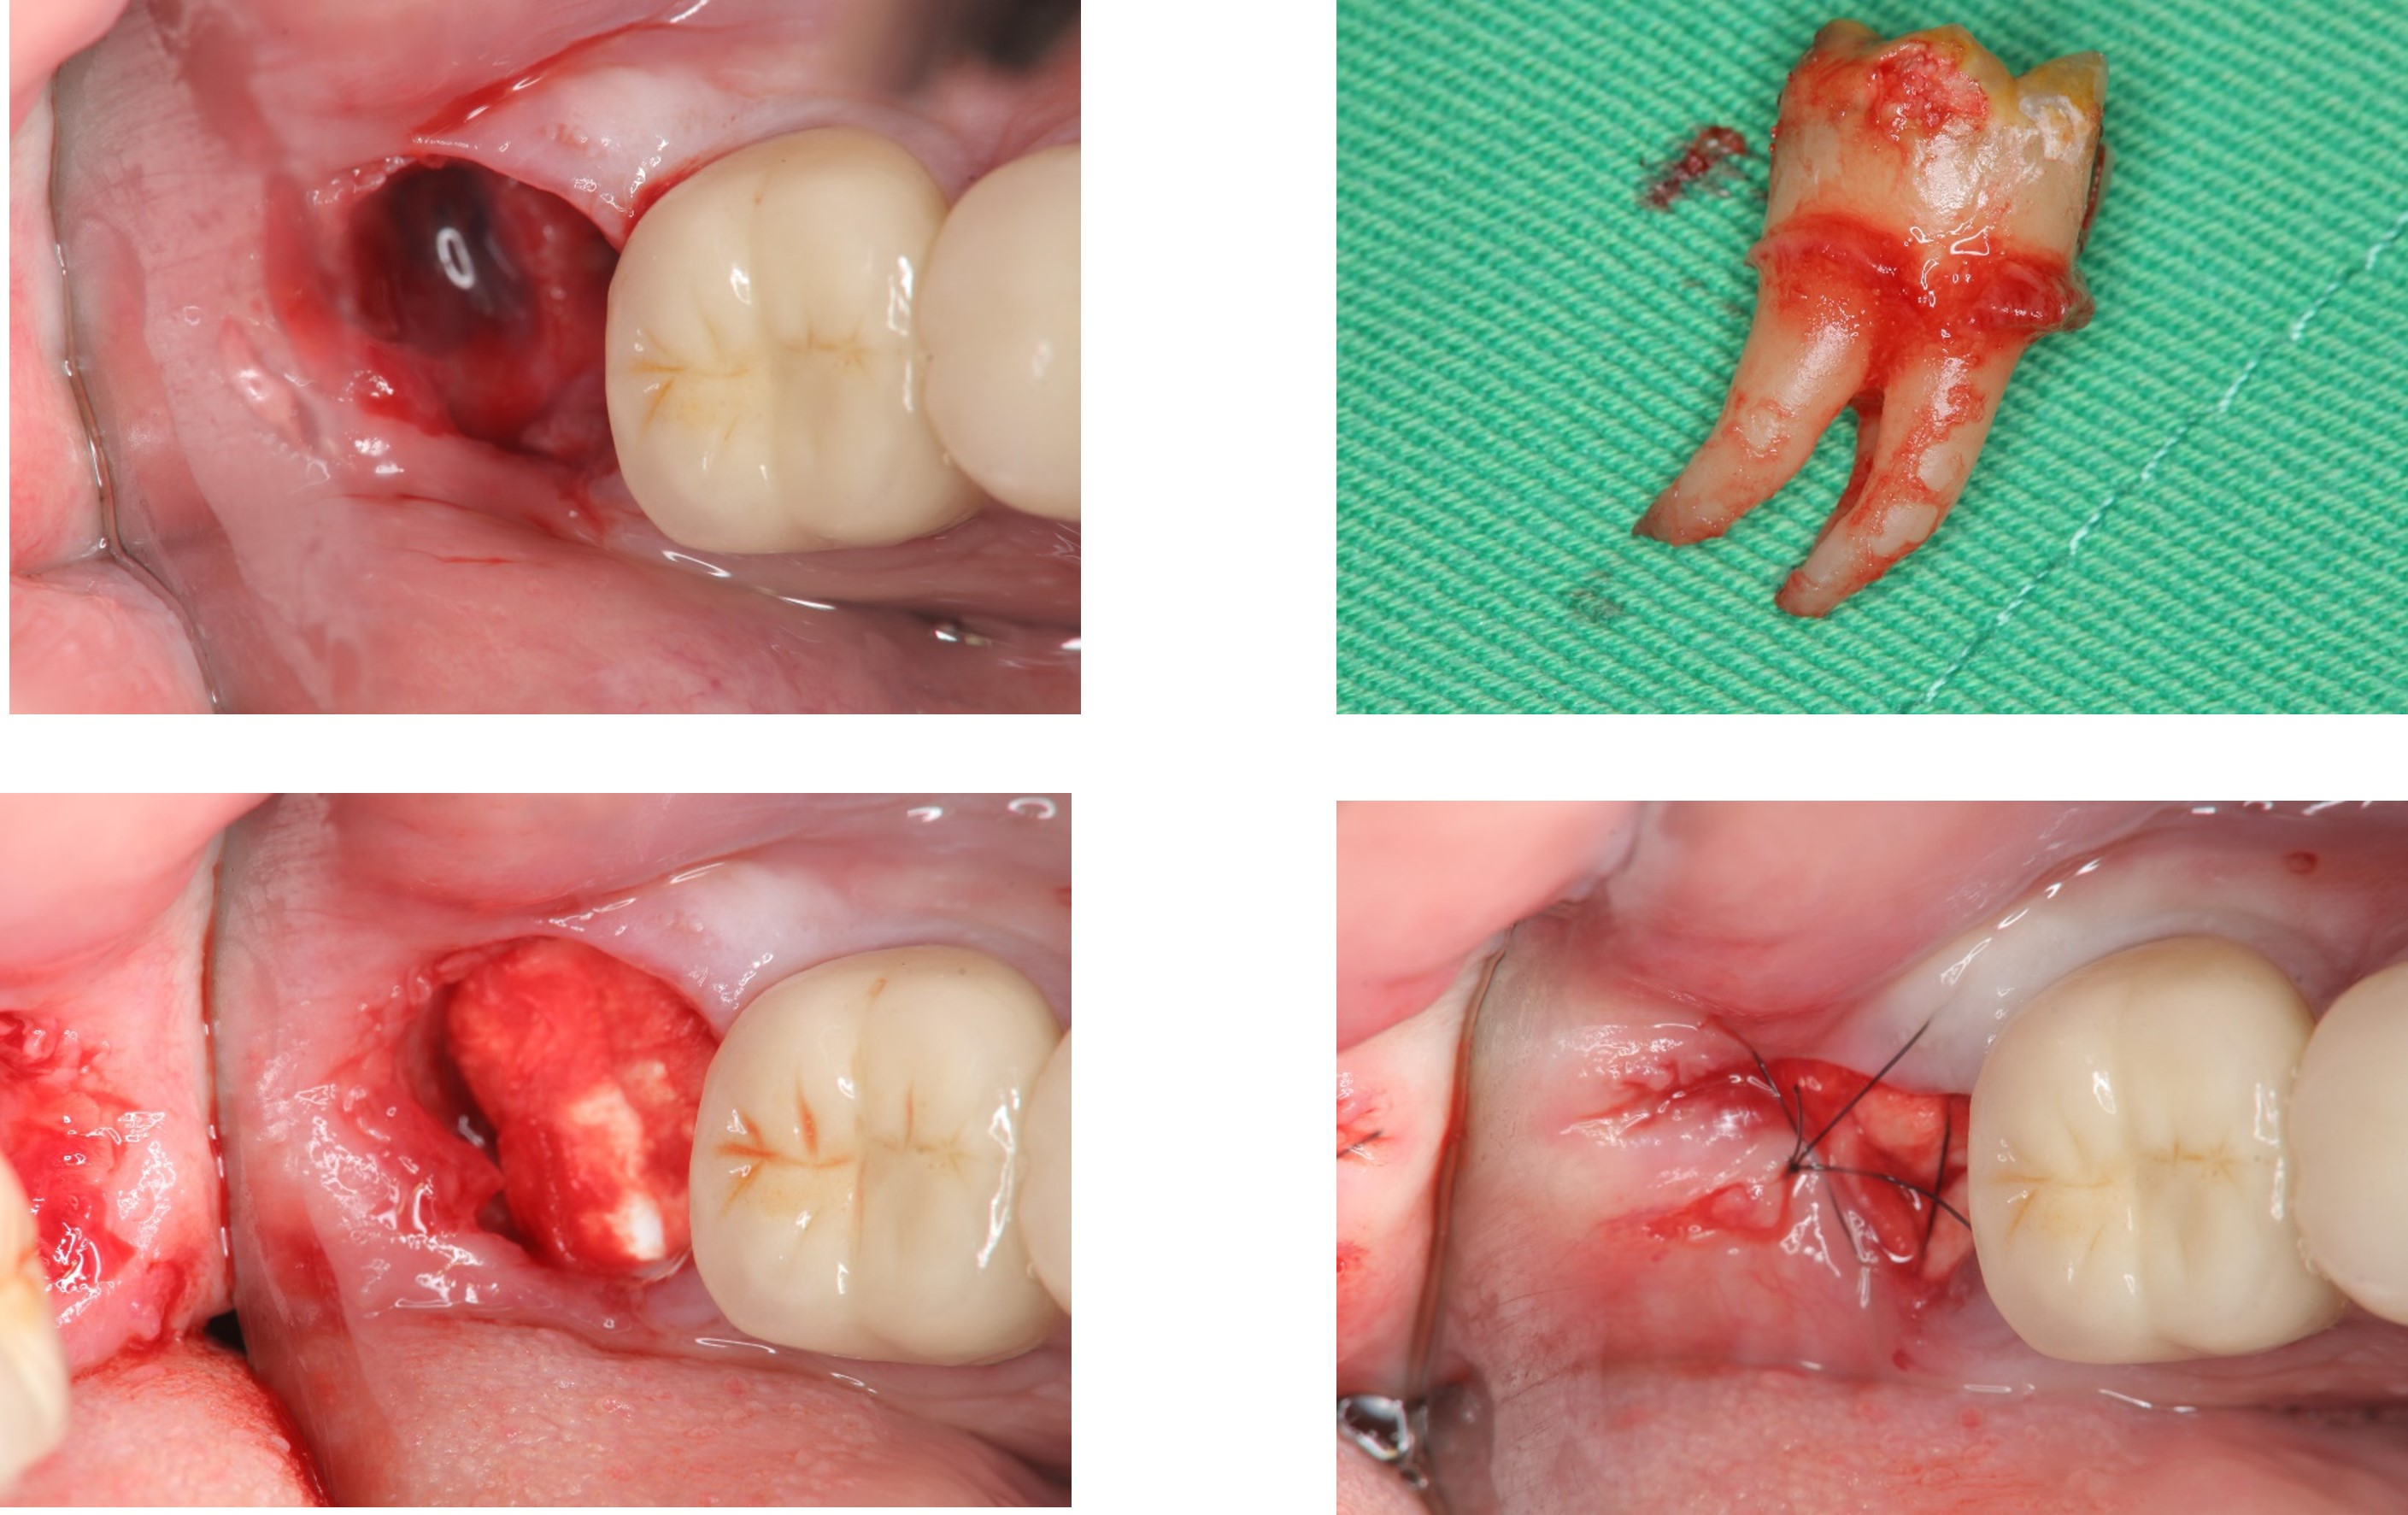

以水雷射切割皮瓣止血、再以手機等拔除阻生齒,並縫合之

1週後傷口癒合良好

使用骨質增生膠原蛋白,來處理拔牙後的傷口。此材料適用的範圍不僅用於拔牙後傷口,所有顎骨中的病灶於手術後皆建議使用。

1 、止血效果:特殊生物材料,能立即止血,且無血塊脫落之困擾。

2、減痛效果:加速傷口癒合,有效減輕疼痛

3 、預防效果:健全牙周組織,避免鄰近牙齒產生牙周病及乾性齒槽炎